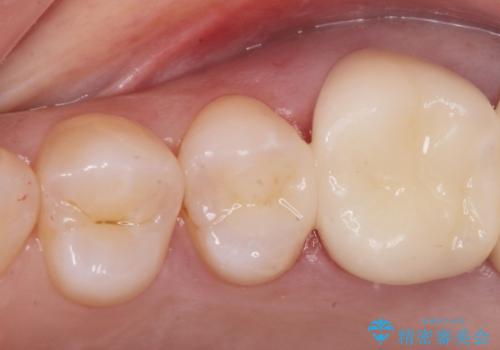

- 銀が目立つので白くしたいとの事で来院。

銀の詰め物を拡大鏡下で取り除き、う蝕がないことを確認してから

ZrCrの被せ物で治療を行いました。

また、一つ手前の歯に小さな虫歯があったため

e-maxインレーでの治療を行いました。